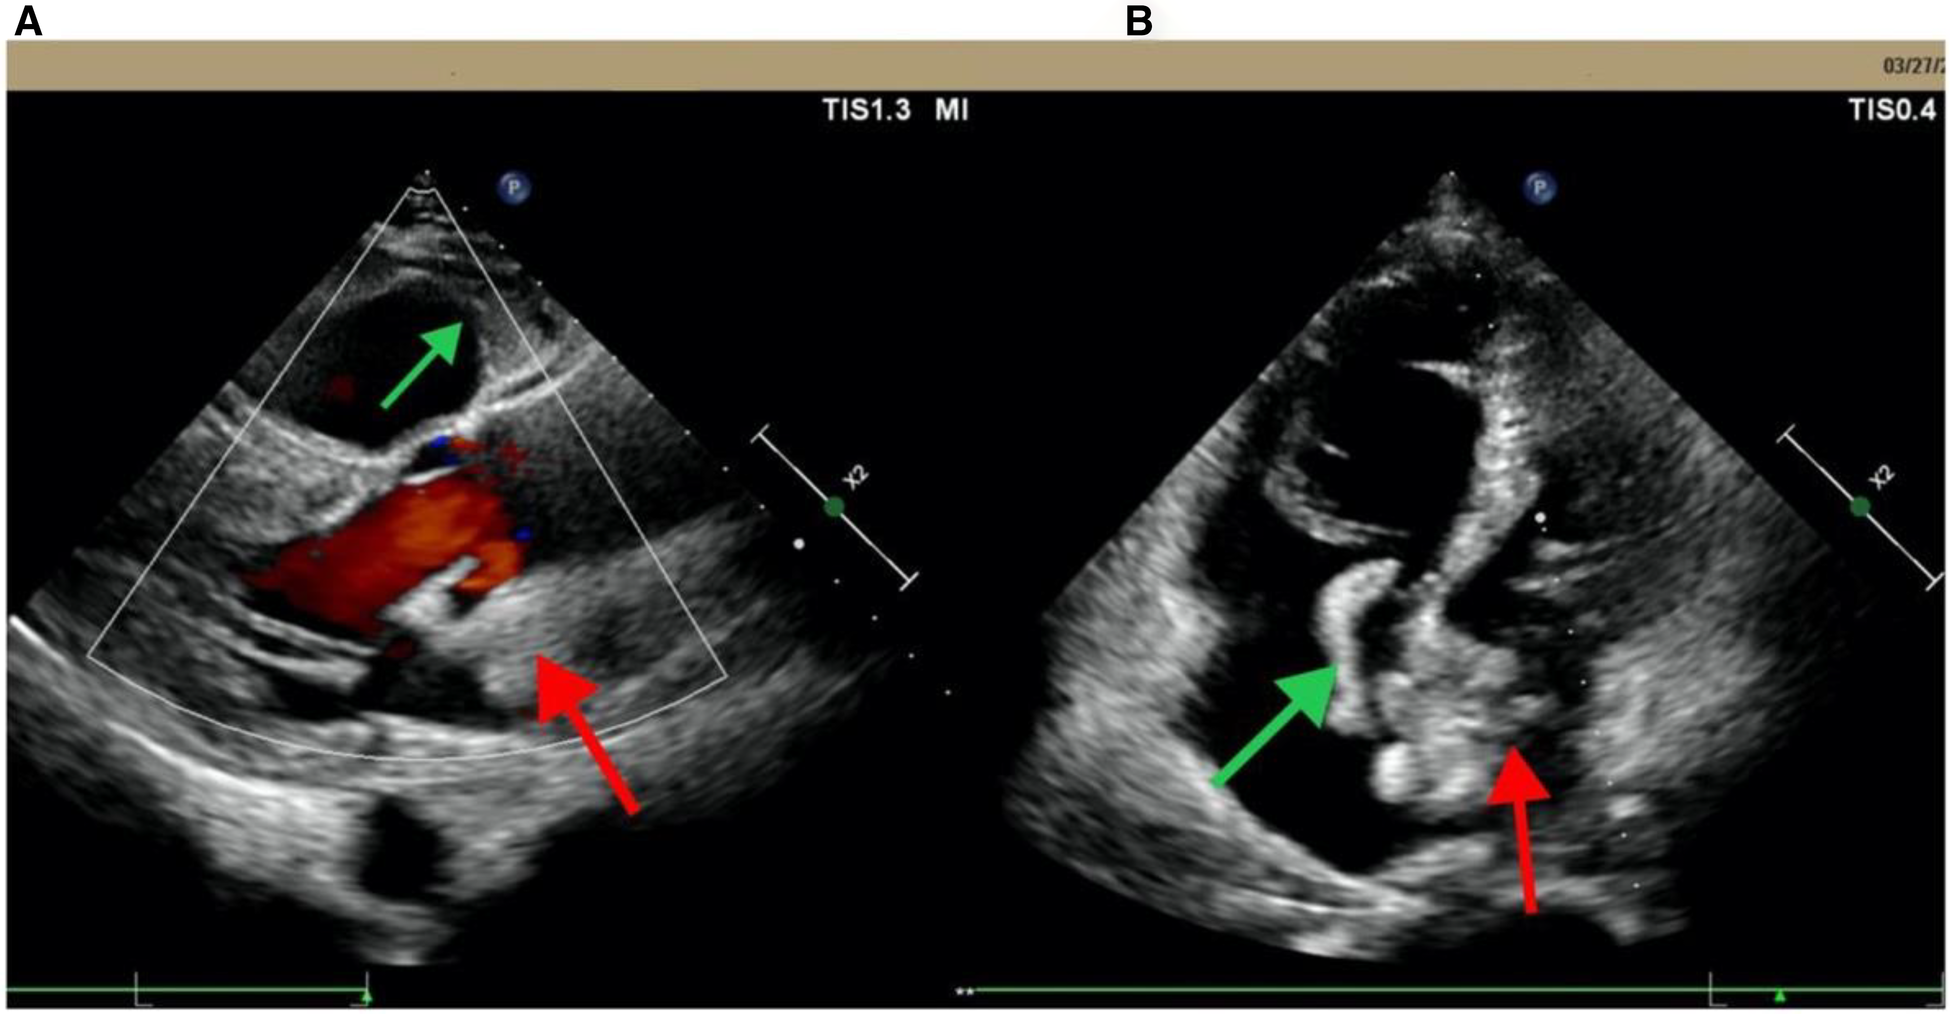

A 62-year-old male patient was admitted to the People's Hospital of Guangxi Zhuang Autonomous Region on March 28, 2023 due to fever and sudden syncope. The patient had a history of hypertension and diabetes for over 20 years without regularly taking antihypertensive and hypoglycemic medications. Additionally, he had had depression for more than 10 years and had been on long-term treatment with sertraline and risperidone. The patient had been admitted to a local hospital due to fever and syncope 2 days previously, where echocardiogram findings indicated an enlargement of the right atrium and ventricle and thrombi within both the left and right atria (Figure 1). After admission, the patient was provided with endotracheal intubation and assisted breathing using a ventilator, antishock therapy, vasopressor therapy with vasoactive drugs, circulation improvement, myocardial nutrition, anticoagulation treatment (drug usage and dosage: rivaroxaban 20 mg Qd), antiplatelet aggregation, acid suppression and gastric protection, and other symptomatic supportive treatments to maintain stability. The patient's condition did not improve, and considering the severity of the condition, the local hospital recommended transfer to a higher-level hospital for treatment.

Figure 1

Echocardiogram from Pingguo People's hospital shows biatrial thrombosis. (A) Parasternal long-axis section; (B) apical four-chamber view. The red arrow points to the left thrombus in the left atrium; the green arrow points to the right atrium thrombus.